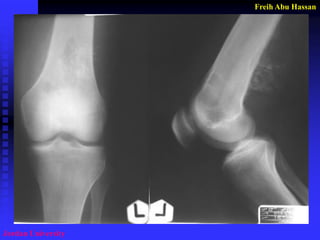

1- Careful studying of the

imagings

2- Small longitudinal incision.

3- Sharp dissection.

4- Plug bone by PMMA.